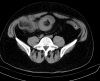

Case presentation: A 46-year-old Caucasian man was transferred from the gastroenterology service to the abdominal surgery service with severe abdominal pain, nausea, and vomiting. An abdominal ultrasound, barium enema, and abdominal computed tomography scan revealed an intraluminal obstruction of his ascending colon. Plain abdominal X-rays showed diffuse air-fluid levels in his small intestine. A double ileoileal and ileocecocolic intussusception was found during an emergent laparotomy. A right hemicolectomy, including resection of a long segment of his ileum, was performed. The postoperative period was complicated by acute renal failure, shock liver, and pulmonary thromboembolism. Our patient was discharged from the hospital after 30 days. An anatomical pathology examination revealed a lipoma of his ileum.